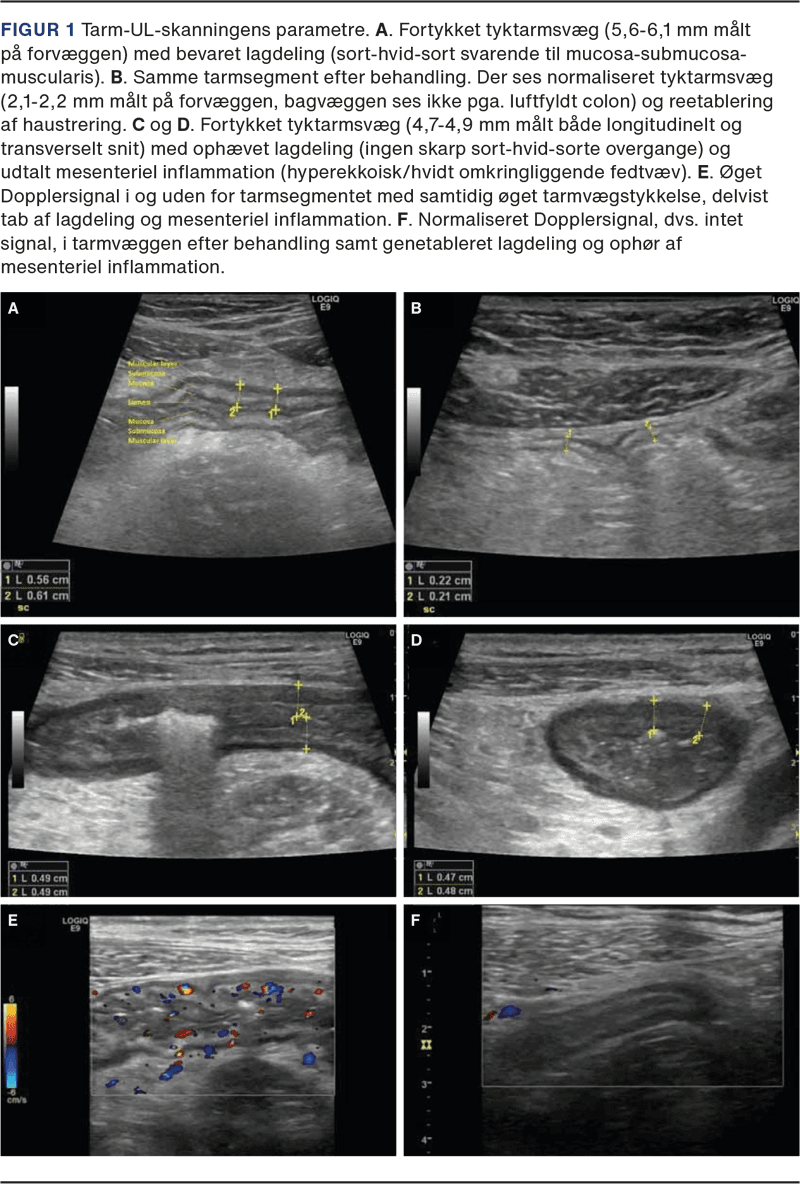

Ved hjælp af TUL identificerer man minimum tre lag i tarmvæggen, og de fremtræder visuelt som »sort-hvid-sort« (Figur 1 A) [17]: Det første hypoekkoiske (dvs. sorte/mørke) lag modsvarer mucosa, mens det næste hyperekkoiske (dvs. hvide/lyse) lag er submucosa. Til sidst ses endnu et hypoekkoisk lag – muscularis propria. Den normale tykkelse af tarmvæggen (bowel wall thickness (BWT)) er < 2,0 mm i både tyk- og tyndtarm (Figur 1 B) [15]. Inflammation vil øge BWT til > 3,0 mm ved både CD og UC (Figur 1 A). Andre mål for inflammation er forstyrret lagdeling i tarmvæggen (dvs. tab af bowel wall stratification) (Figur 1 C + D) samt øgning i CDS (Figur 1 E + F). Endelig ses mesenterial fedtproliferation (Figur 1 C + D) mest udbredt ved CD og forstørrede lymfeknuder i krøset. Stenoser, fistler og abscesser identificeres også ved TUL, og det er muligt at kvantificere en eventuel præstenotisk dilatation [18]. Der er udviklet forskellige aktivitetsscorer, hvoraf International Bowel UltraSound Segmental Activity Score (IBUS-SAS) er valideret til CD [19], mens Milan Ultrasound Criteria (MUC) er valideret til UC [20]. Begge er signifikant korreleret til endoskopiske fund. På den baggrund har vi udviklet en systematisk deskriptiv standardrapport, som indeholder de essentielle informationer og resultater af en TUL ved både CD og UC (Tabel 1).